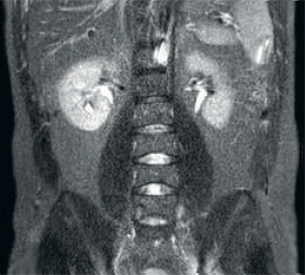

Result: Noisy images using identical scan parameters

Increased consistency and enhanced image quality dStream RF receive technology digitizes the MR signal directly in the RF coil, resulting in an increase of up to 40% more SNR* throughout the whole image volume. Simplified workflow and improved throughput Posterior coil integrated into the tabletop eliminates coil handling in 60% of exams. Lightweight conforming anterior coils and singlehanded, single cable coil connections add to operational ease.